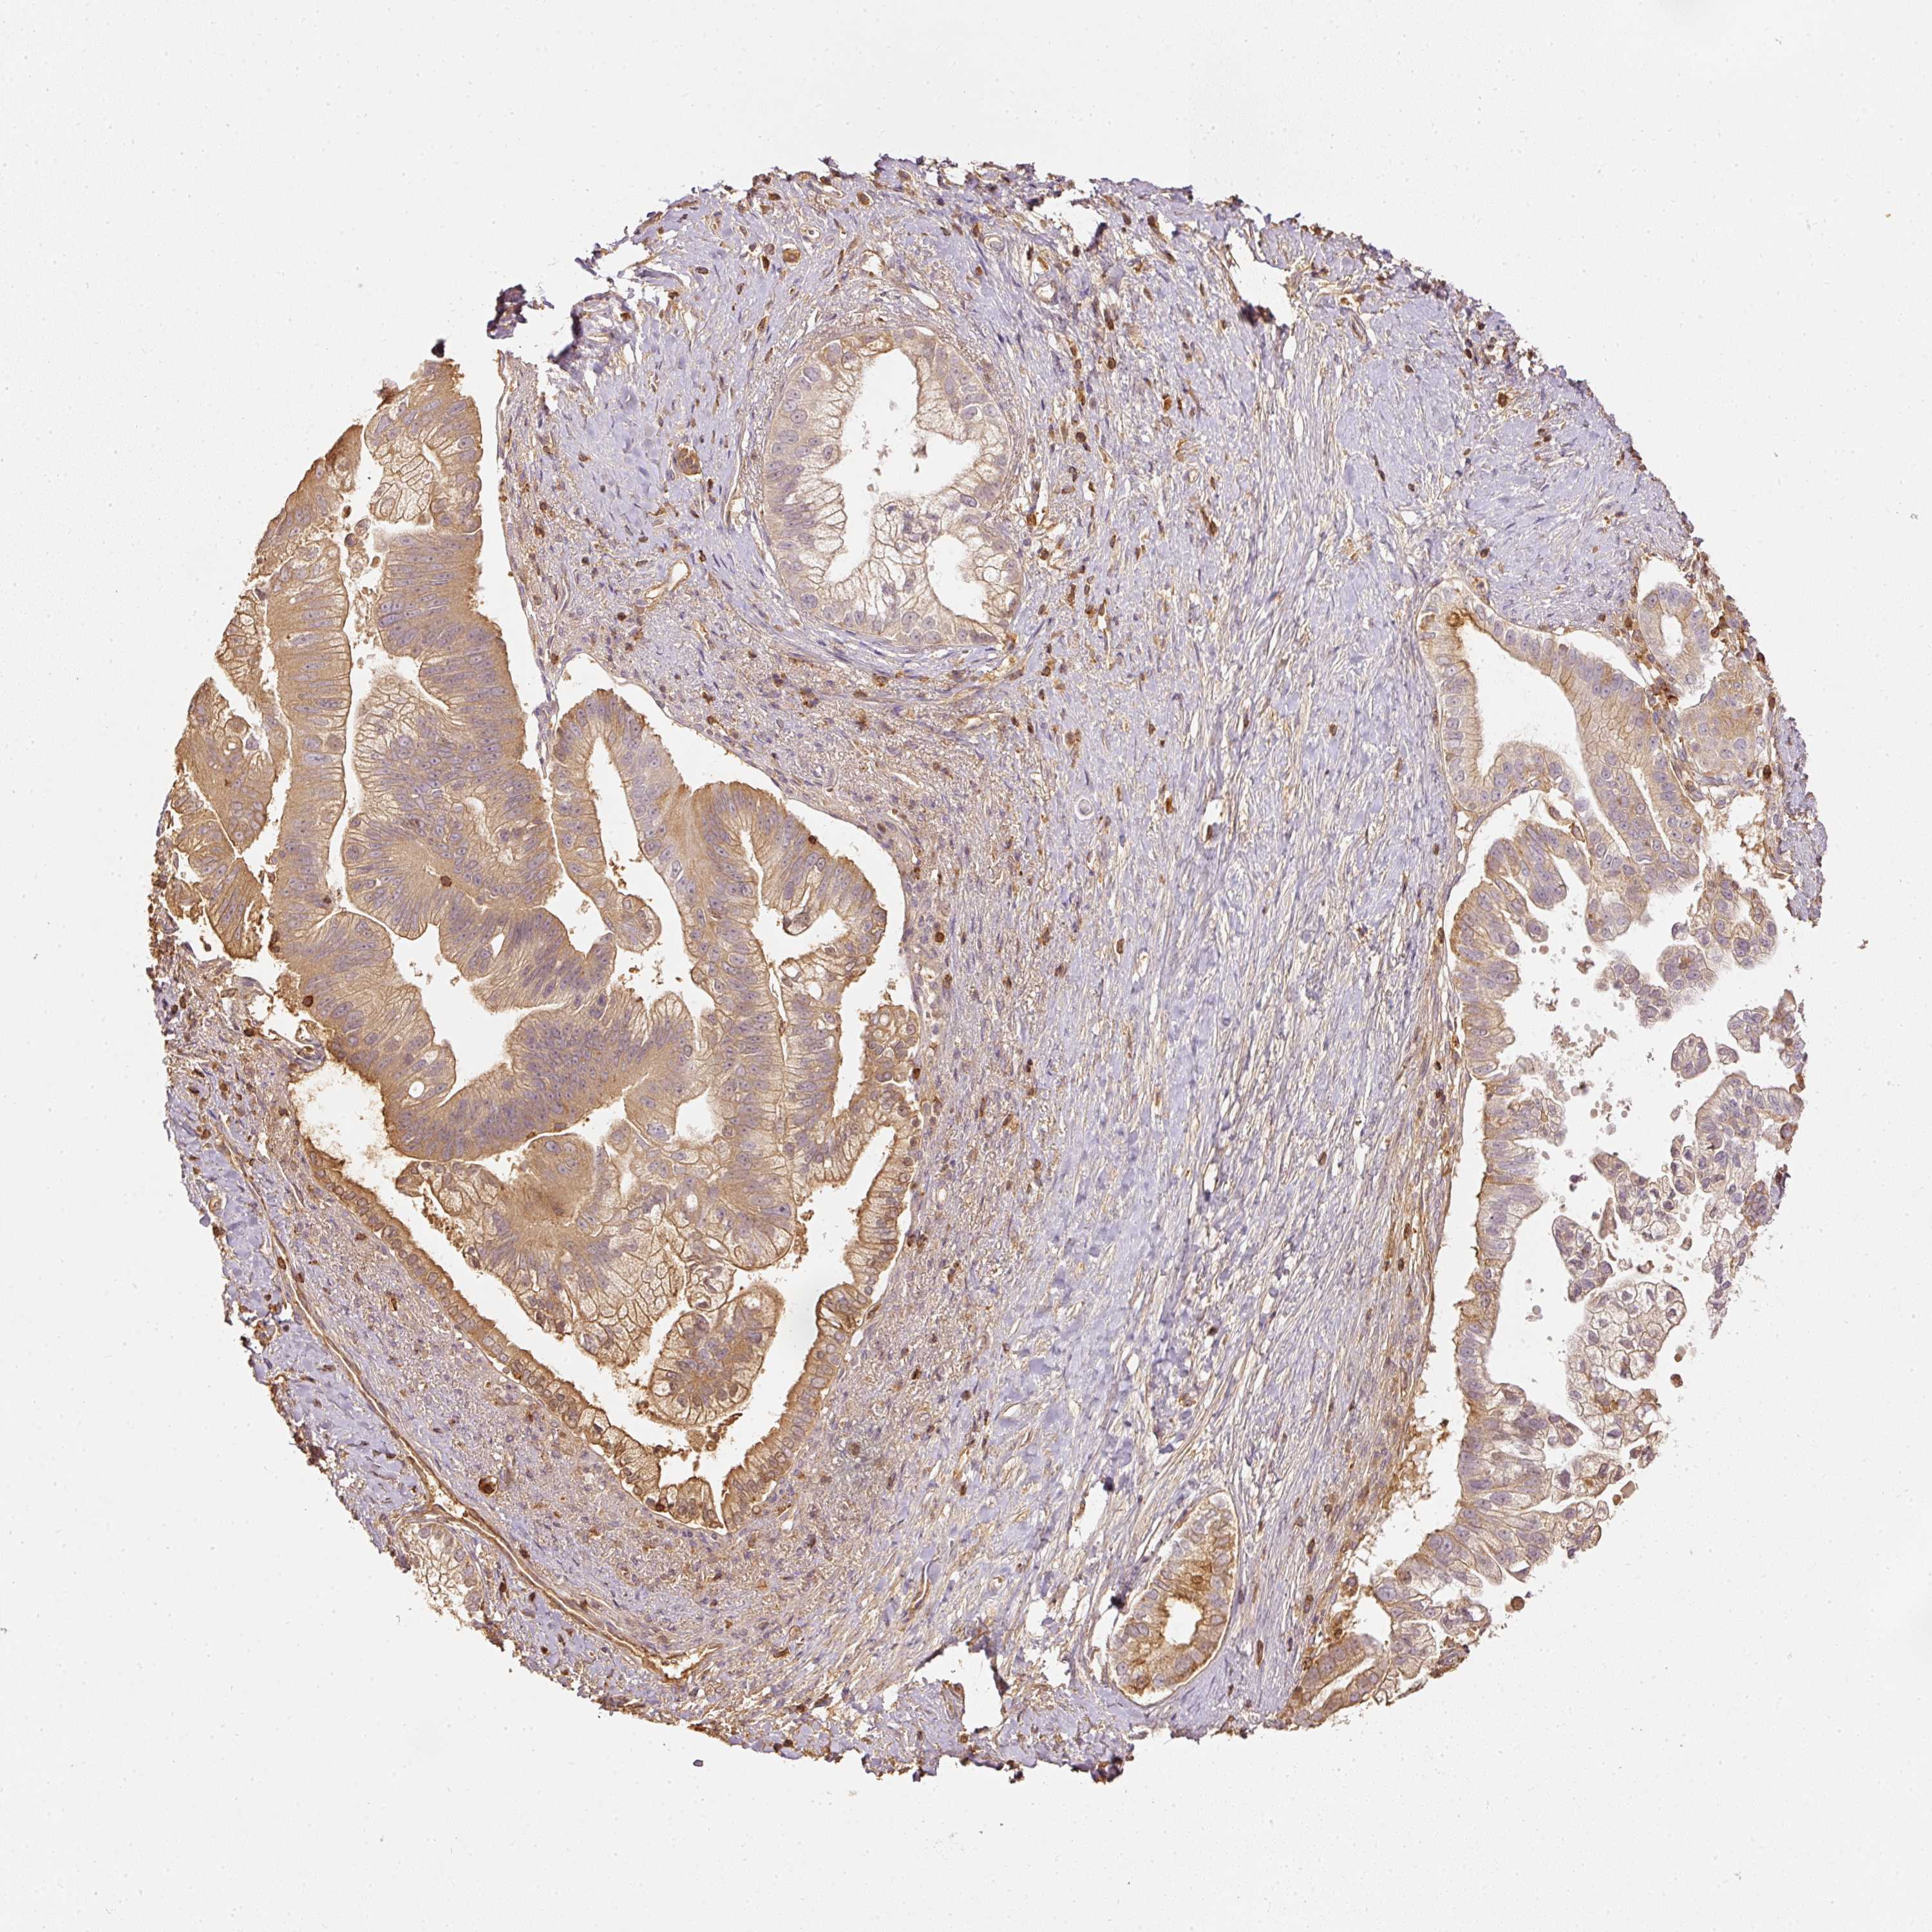

PANCREATIC CANCER - Protein expressioni

A mouse-over function shows sample information and annotation data. Click on an image to view it in a full screen mode. Samples can be filtered based on level of antibody staining by selecting one or several of the following categories: high, medium, low and not detected. The assay and annotation is described here.

Note that samples used for immunohistochemistry by the Human Protein Atlas do not correspond to samples in the TCGA dataset.

Antibody stainingi

Antibody staining in the annotated cell types in the current human tissue is reported as not detected, low, medium, or high, based on conventional immunohistochemistry profiling in selected tissues. This score is based on the combination of the staining intensity and fraction of stained cells.

Each image is clickable and will lead to virtual microscopy that enables deeper exploration of all samples and also displays staining intensity scores, fraction scores and subcellular localization as well as patient and tissue information for each sample.

Antibody HPA018849

Antibody HPA019536

Antibody CAB033987

Adenocarcinoma, NOS